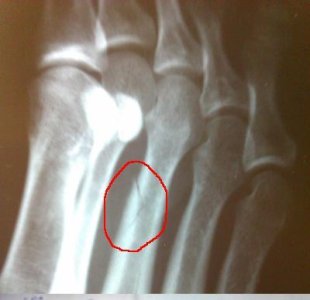

Мне 23, занимаюсь ирландскими танцами. Неудачно прыгнула, и как результат - перелом диафиза 3 плюсневой без смещения.

Вот снимок x-ray1.JPG

Отёка, синяка, никаких внешних изменений не было. До обращения в травмпункт наблюдалась только несильная, но чувствительная боль при отрыве стопы от пола. На следующий после перелома день на стопу был наложен гипс (лангета), доктор сказал, что на 3 недели. На повторном приёме (через 5 дней) было велено оставить костыли и пользоваться тростью или 1 костылём.

На данный момент передвигаюсь по дому вовсе без дополнительной опоры (хотя, конечно, медленно и осторожно..) так как "запакованная" нога совсем не болит, не отекает, не ноет.

Вопрос заключается в следующем: Как скоро после снятия гипса можно будет без риска осложнений и повторной травмы возобновить нагрузки на стопу?